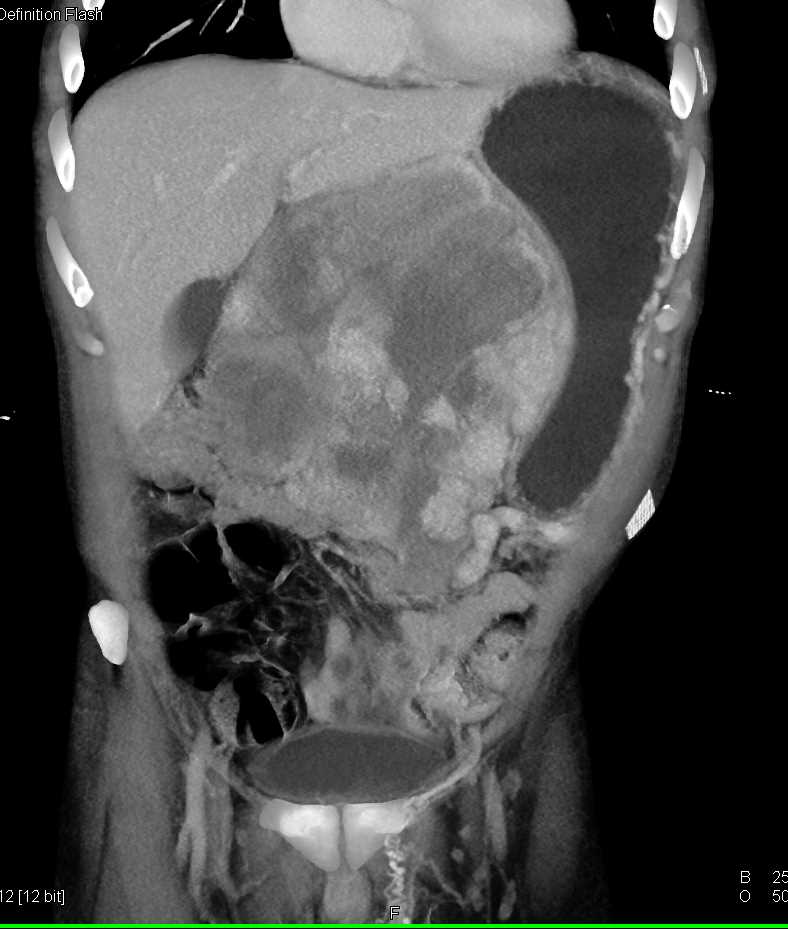

Lagre Gastric GIST Tumor